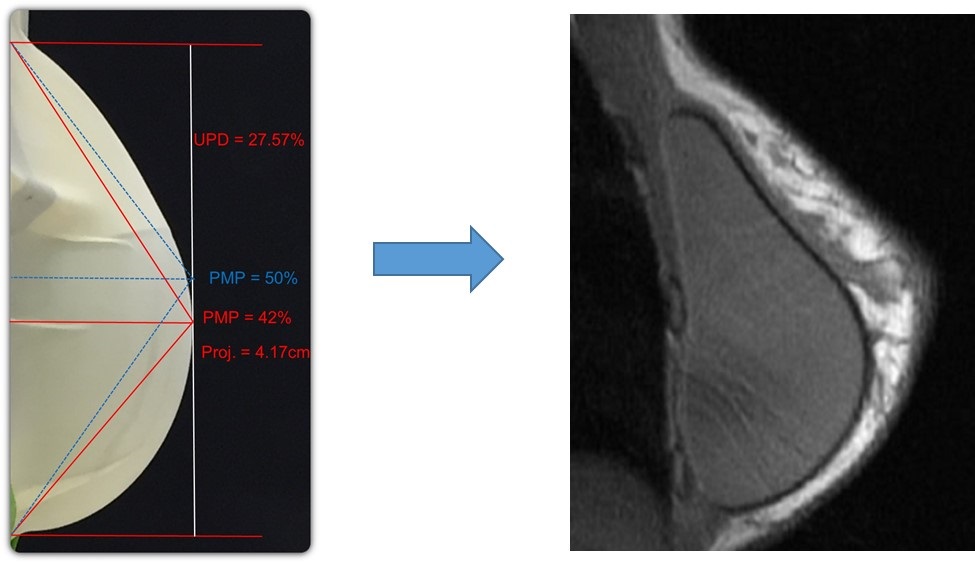

In addition to the anticipated safety advantages, our ProgressiveGel family, provides for movement characteristics that resemble natural breast tissue. Our later generation Ergonomix products, further mimic natural tissue, with a maximum point of projection that shifts downward to create a natural human breast shape when a patient is standing. This allows our Motiva Implants to provide the more natural aesthetics of “shaped” or “teardrop” implants without the risk of associated drawbacks such as breast deformation from rotation and unnaturally hard tactile feel. The images below illustrate the implants’ ability to change shape depending on the patient’s positioning.